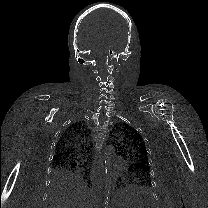

Image Attribution

Coronal plane of bone-enhanced CT scan of cadaver (SR060). Data collected by Noa Nuzov on 06/06/2025.